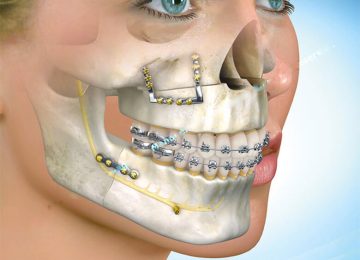

Desconforto funcional na região orofacial, associado a dificuldades mastigatórias e episódios recorrentes de dor

A atuação em cirurgias da face exige formação especializada, experiência clínica e uma abordagem integrada entre Odontologia e Medicina.

Somos especialistas no tratamento e cirurgia do rosto, maxilares, boca e estruturas da cabeça e pescoço.com atuação tanto em consultório quanto em ambiente hospitalar.